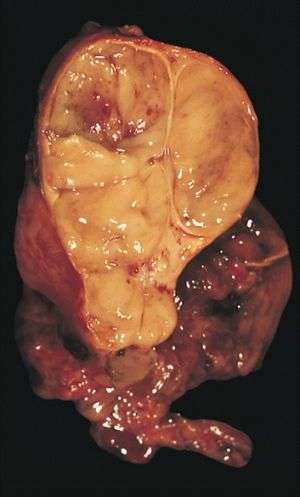

Gallery

An encapsulated cystic thymoma.

A locally invasive circumscribed thymoma (mixed lymphocytic and epithelial, mixed polygonal and spindle).- Histopathological image of thymoma type B1. Anterior mediastinal mass surgically resected. Hematoxylin & eosin stain.